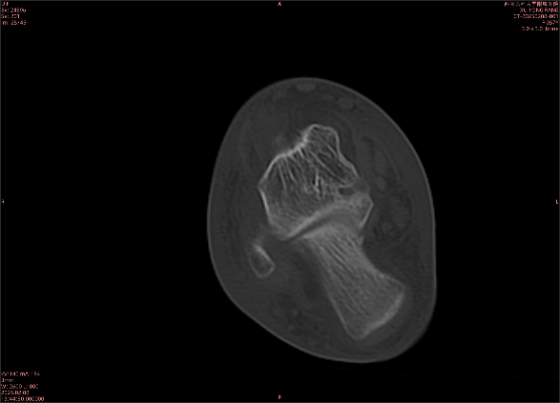

舉例圖像

圖1

專業(yè)解釋看不懂沒關(guān)系,大家看圖1和圖2就可以了,這是同一個(gè)患者跟骨的磁共振和CT圖像,圖1的紅色箭頭指示的黑線就是磁共振圖像顯示的骨折線,一目了然。而對比圖2的CT圖像上并未顯示異常。

這下大家明白了吧,如果懷疑隱匿性骨折優(yōu)先選擇磁共振檢查